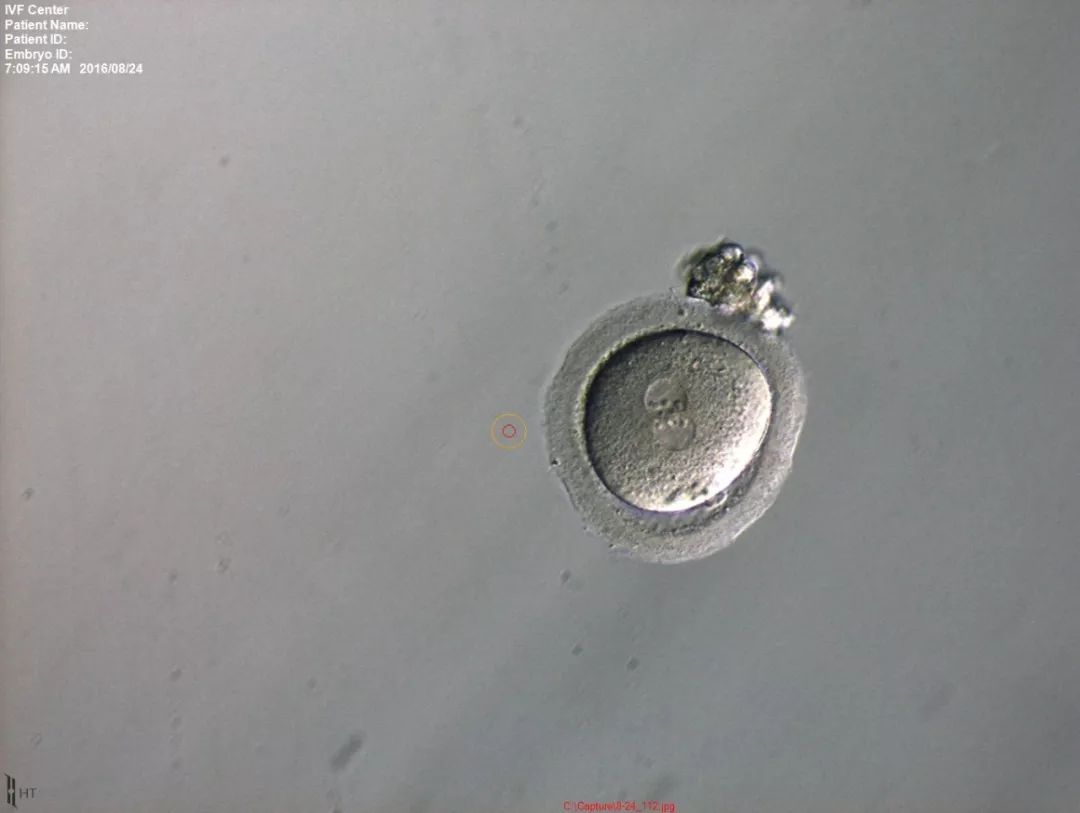

取卵日是在B超引导下经阴道穿刺取卵,大概二十分钟即可做完,术前用镇痛药,故不必紧张,除特殊情况下,医生会建议麻醉取卵外,绝大多数病人不需要麻醉即可顺利完成取卵。